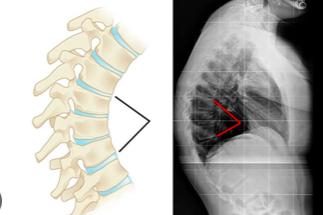

Qual é o ápice comum da cifose na Doença de Scheuermann?

Geralmente entre T7-T9 ou T8-T10.

Quais são os sinais clínicos da Doença de Scheuermann?

Os sinais incluem cifose angular torácica ou toracolombar, hiperlordose lombar compensatória, músculos encurtados e, em cerca de 30% dos casos, escoliose.